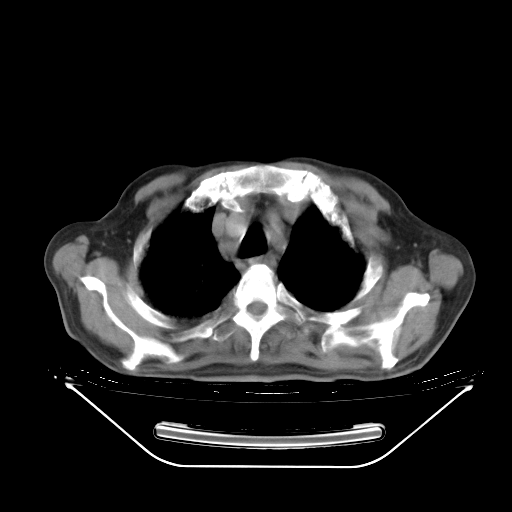

今天复查肺部CT,发现双肺广泛磨玻璃样改变。所以我把3月19日和5月9日相隔50天的肺部CT上传。请大家会诊。

2009年3月19日肺部CT片。

2009年3月19日肺部CT

胸腹部CT,诊断意见:左上肺叶钙化灶、左侧胸膜局限性增厚并钙化、胆囊炎。描述部分肺组织呈磨玻璃样改变。

大致读了系列胸部CT:纵隔窗无明显异常,肺窗:从4、27至今:主要是双肺中下野外带可见毛玻璃样改变,目前处于急性肺泡炎阶段,至于原因考虑1、结替组织或胶原血管性疾病所致?2、恶性疾病如恶组在肺部所致的表现或细支气管肺泡癌?3、药物或其它原因如肺蛋白沉着症所致肺泡炎目前不太可能?总之,明天就去请我院的呼吸科、感染科、血液科和临免专家会诊哈。